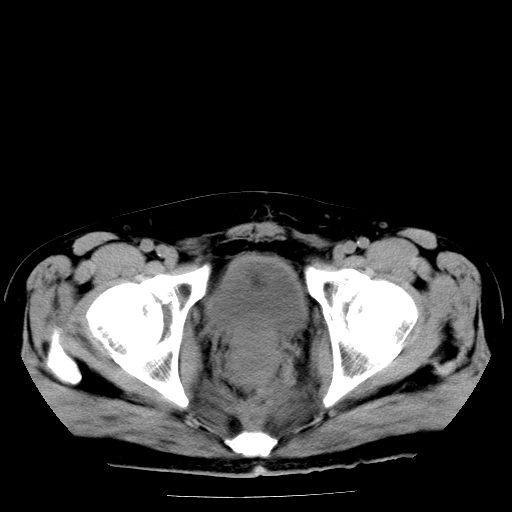

男,66岁,直肠癌术后一个月,化疗前ct检查。

前列腺大,直肠壁厚,造瘘术后

直肠癌造瘘术后改变,周围淋巴结转移

前列腺肥大

直肠癌造瘘术后改变,盆腔多发淋巴结转移

直肠癌造瘘术后改变,直肠周围软组织增厚,盆腔多发淋巴结转移。前列腺肥大。